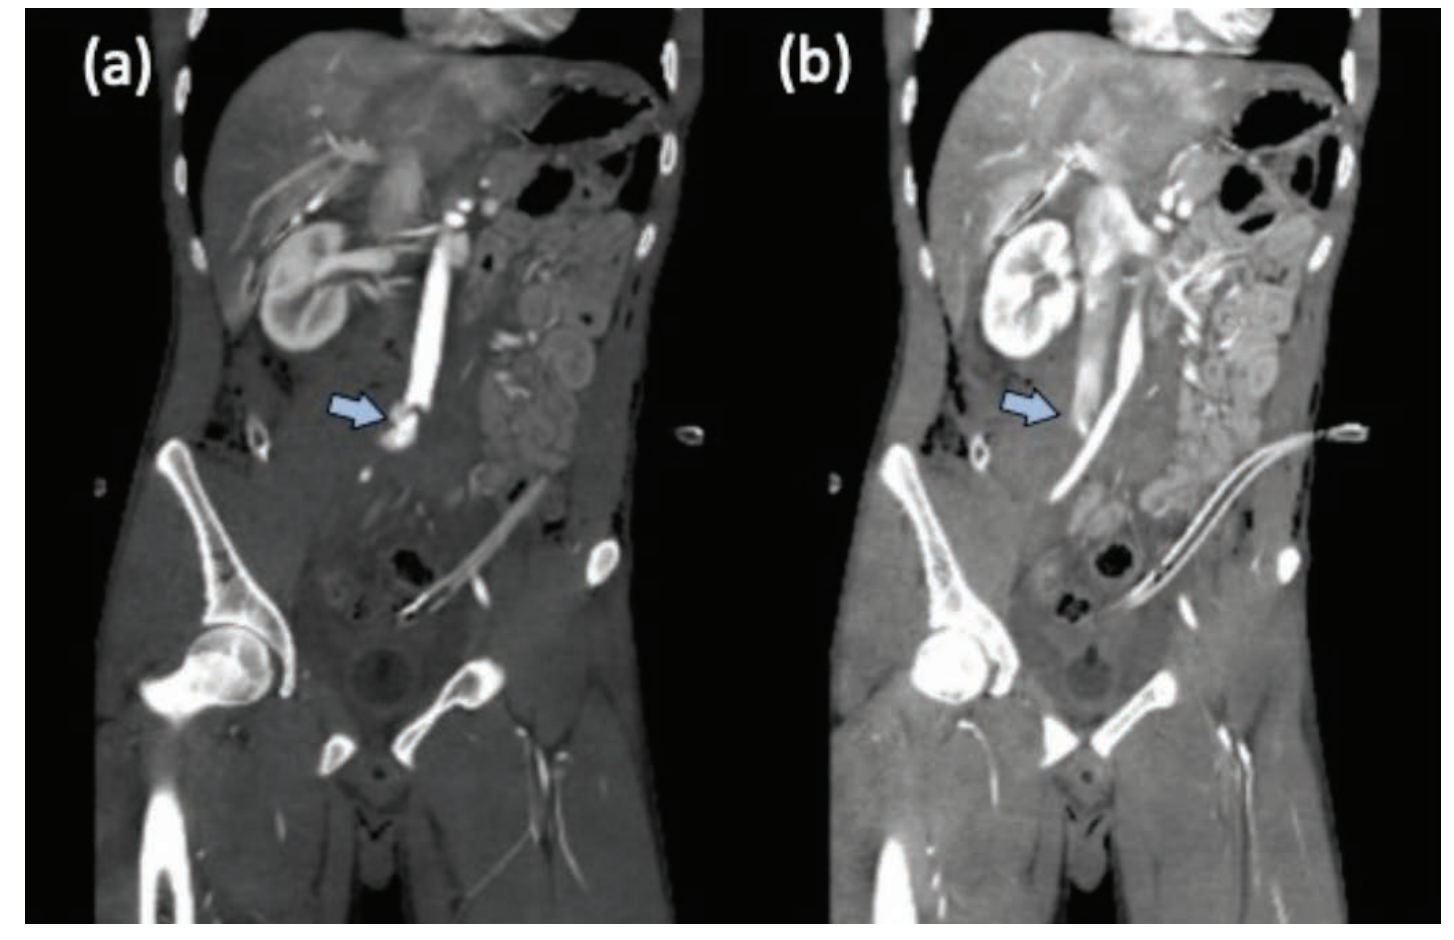

The patient had persistent hypotension in the immediate post-operative period and was referred to our center. On arrival, he was stabilized with intravenous fluids and one pint of blood. A wound was noted in the left iliac fossa, corresponding to the history of penetrating injury. His left side intra-abdominal drain had 200 mL frank blood on arrival and 20 mL additional blood per hour. A CT angiogram showed a pseudoaneurysm measuring approximately 20 mm × 10 mm arising from the right fifth lumbar artery, coming from the median sacral artery (Figure 2A). The pseudoaneurysm had a fistulous communication with the inferior vena cava (Figure 2B), and there was a diffuse hematoma in the surrounding retroperitoneum. The patient underwent angiography through a right femoral access, which confirmed the findings from on CT. The pseudoaneurysm was embolized using 4 mm × 6 mm MicroNester pushable coils (Cook Medical) that reduced the flow across the fistula. The residual stump of fistulous tract was embolized with 20% Histoacryl (B Braun Melsungen AG) (Figure 3). Post procedure, there was no output of blood from the drain. The patient had an uneventful recovery and was discharged in 8 days.